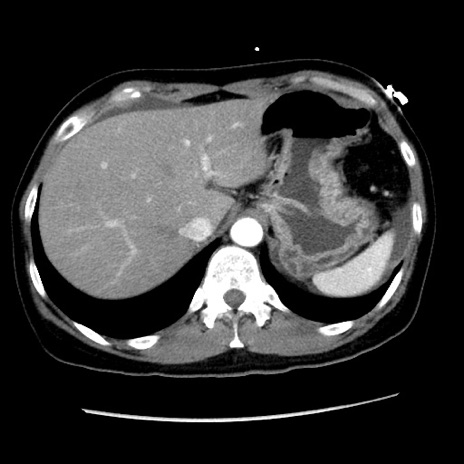

矢状断像